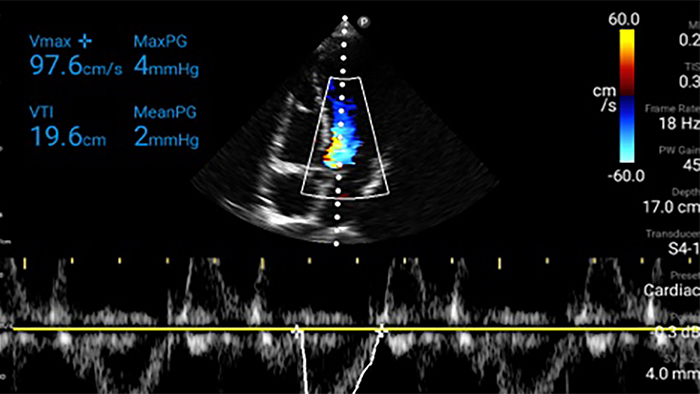

Lumify S4-1 broadband phased array transducer

• 4 to 1 MHz extended operating frequency range • 2D, color Doppler, M-mode, advanced XRES and multivariate harmonic imaging • High-resolution imaging for abdominal and cardiac applications: Cardiac, OB/GYN, Lung, Abdomen and FAST imaging preset optimizations